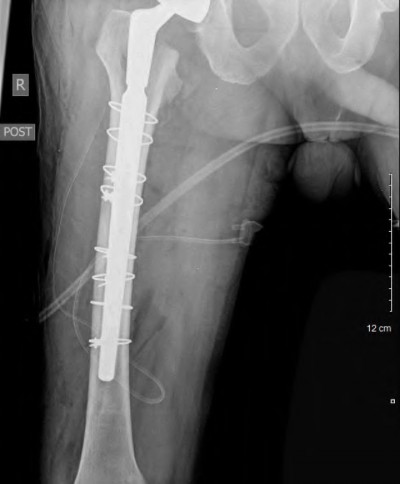

A 72-year-old female falls and sustains a periprosthetic femur fracture around her cementless total hip arthroplasty. Radiographs reveal a fracture extending just distal to the tip of the stem. The stem is radiographically loose, but there is excellent proximal and distal bone stock. According to the Vancouver classification, what is the fracture type and the recommended surgical treatment?

Explanation

A 75-year-old female sustains a fall 5 years after a cementless THA. Radiographs show a periprosthetic femur fracture occurring around the stem tip. Intraoperative assessment reveals the stem remains firmly fixed in the metaphysis, and the proximal bone stock is adequate. According to the Vancouver classification, what is the fracture type and the standard recommended treatment?

A 72-year-old female presents with acute thigh pain and an inability to bear weight after a minor fall, 10 years post-THA. Radiographs demonstrate a fracture around the tip of the well-fixed femoral stem, extending into the diaphysis. The bone stock proximally remains intact. Which principle must be strictly adhered to during the surgical fixation of this fracture?